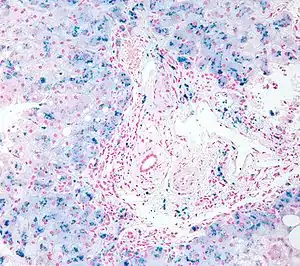

Гемохроматоз (також — пігментний цироз печінки, бронзовий діабет, синдром Труаз'є-Ано-Шоффара, сидерофілія) — спадкове, генетичне захворювання, під час якого організм людини починає накопичувати залізо, що надходить з їжею.

Супроводжується поширеним зростанням відкладання залізомісткого пігменту у тканинах деяких органів з наступними фіброзними змінами в них та функціональними порушеннями.

Первинний відносять до ферментопатій та розглядають як вроджене, конституційно зумовлене захворювання, при якому у тонкій кишці всмоктується значно більше заліза, аніж у нормі. Воно у надлишку скупчується у тканинах та органах у вигляді гемосидерину, спричиняючи в них запально-склеротичні зміни.

Діагноз підтверджують при визначенні підвищеного вмісту заліза у сироватці крові (більше 30 мкмоль/л). У сумнівних випадках застосовують морфологічне дослідження тканини печінки з біопсії.